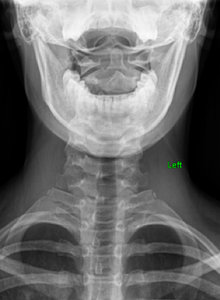

FIG 3 Lateral cervical view revealing a straight cervical spine.

I then looked at her X-rays. The most important view is the A-P L-S. We took the first series barefoot. On this view, I first looked at femoral head height. She had a 6.8 mm femoral head height difference, higher on the right. (Fig. 2) On her lateral L-S view, she had a lumbarization, removing the ability to know exactly what her Ferguson's center of gravity showed, as well as her sacral base angle. On lateral cervical (Fig. 3), she had a straight cervical spine, often associated with chronic headaches. The open-mouth view (Fig. 4) showed the significant imbalance between atlas and axis.